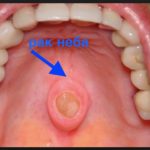

Плоскоклеточный рак десны – основная разновидность этого недуга, которая тяжело протекает, вызывая активное метастазирование в лимфоузлы и на большую глубину. Основной признак, по которому специалисты ставят диагноз – лейкоплакия. Со стороны это выглядит, как белые пятна на слизистой оболочке, которые образуются из остатков отмершего эпителия. Бывает так, что ничего не указывает на рак десны, стадии малозаметны, а симптомы не привлекают внимание. Об опухоли пациент узнает только на приеме у доктора. Но чаще небольшие изменения в состоянии присутствуют.

Каждому человеку важно знать, как на любом этапе выглядит рак десны и как проявляется – это поможет вовремя насторожиться и проконсультироваться с врачом. Опухоль замечают не сразу, потому что небольшое уплотнение не ощущается, а эстетически оно малозаметно, и человек не придает ему значения. Когда заболевание прогрессирует, образование быстро разрастается, сопровождаясь определенными признаками. Когда у человека рак десны, начальная стадия, симптомы включают в себя появление на тканях белесых или багровых пятен. Также наблюдается:

Очень важно знать, как рак десны выглядит и как проявляется на всех стадиях, чтобы вовремя обратить внимание на тревожные симптомы. На начальном этапе опухоль небольшая – ее размер доходит до 1 см в диаметре, а внешне она малозаметна. Второй этап – фаза активного роста образования. Возникает рак десны, 2 стадия которого характеризуется углублением очага заболевания примерно на 1 см. Также появляется первый метастаз, хотя это может произойти только на третьей стадии, когда метастазы обнаруживают в лимфоузлах со стороны пораженной области.

Опасно лечить зубы в этот период, потому что инфекция будет накапливаться еще быстрее. При наличии подозрения на признаки рака десны обычно назначают цитологическое исследование, биопсию. В первом случае берут соскоб со слизистой оболочки, а во втором – фрагмент материала около опухоли, анализ которого позволит определить характер образования. Если есть подозрение на рак десны, фото стадий можно получить при магнитно-резонансной томографии, где пораженные зоны выделены цветом. Состояние челюстей отслеживают в ходе ортопантомограммы.